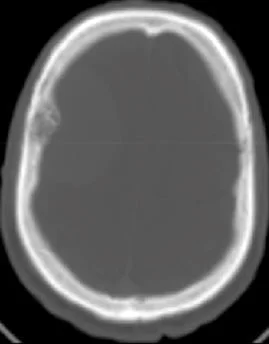

Un méningiome peut être diagnostiqué au scanner où il apparaît comme une masse ronde à la périphérie du cerveau, avec un épaississement de l’os au niveau de sa base d’insertion sur la méninge.

Il est plus fréquemment retrouvé sur une IRM sous forme d’une masse “blanche” après injection du produit de contraste intraveineux et entourée d’un œdème. Les méningiomes peuvent se rencontrer dans différentes localisations intra-crâniennes, plus ou moins facilement accessibles et qui conditionneront la technicité et les risques du geste qui vous sera proposé par votre chirurgien.

frontal droit